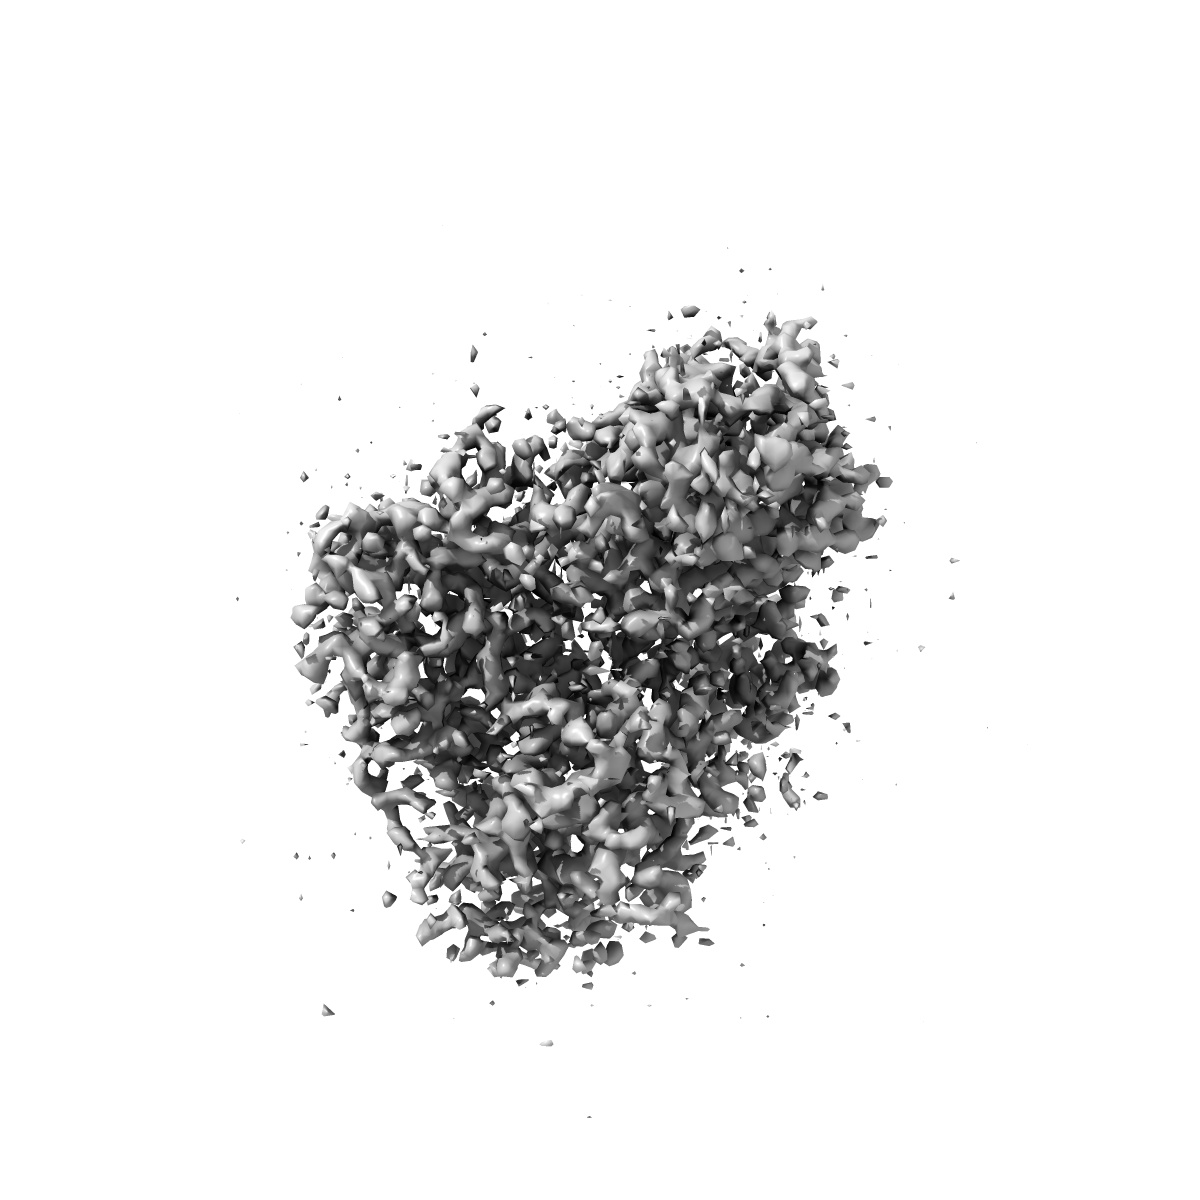

Intermediate-resolution cryo-EM map of CAK bound to ICEC0942 (grid VC13-1, 4hr collection)

Single-particle3.2 Å

Sample: CDK-activating kinase

High-resolution cryo-EM of the human CDK-activating kinase for structure-based drug design.